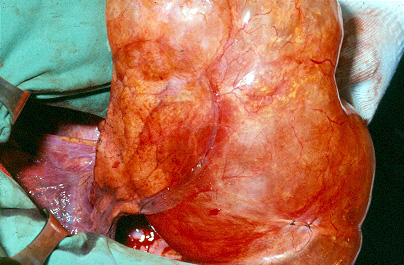

Group III: multiple bullae with underlying lung diffusely emphysematous (Figure 2)

| Figure 1: Operative view at thoracotomy of a single bulla with normal underlying lung. | Figure 2: Operative view at thoracotomy of multiple bullae with underlying lung with diffuse emphysema. |